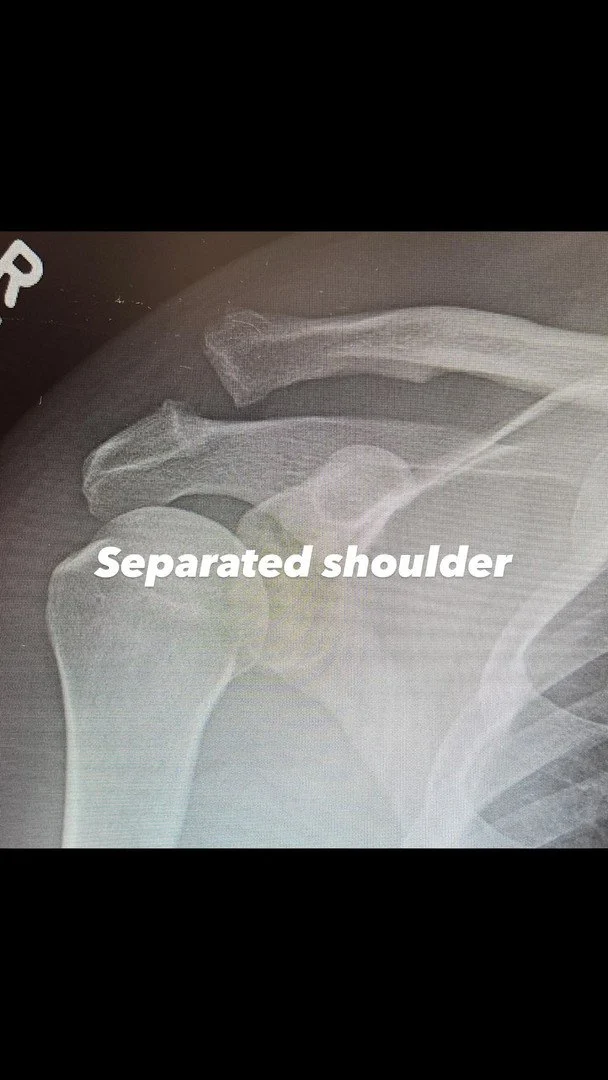

Плече Ченнінга Татума після операції. Фото: instagram.com/channingtatum

Актор також поділився рентгенівськими знімками плеча - до та після хірургічного втручання. Водночас він не став розкривати, за яких обставин отримав травму. Ченнінг лише зазначив, що попереду на нього чекає непростий період відновлення, але він налаштований упоратися з усіма труднощами.